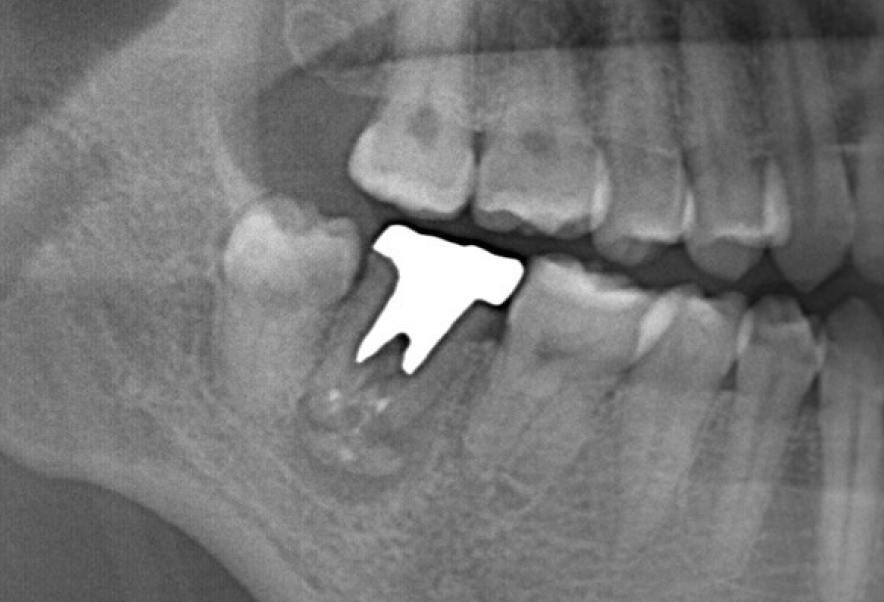

Before

After

他院で根管治療後自費補綴を装着、膿んできた歯の再治療